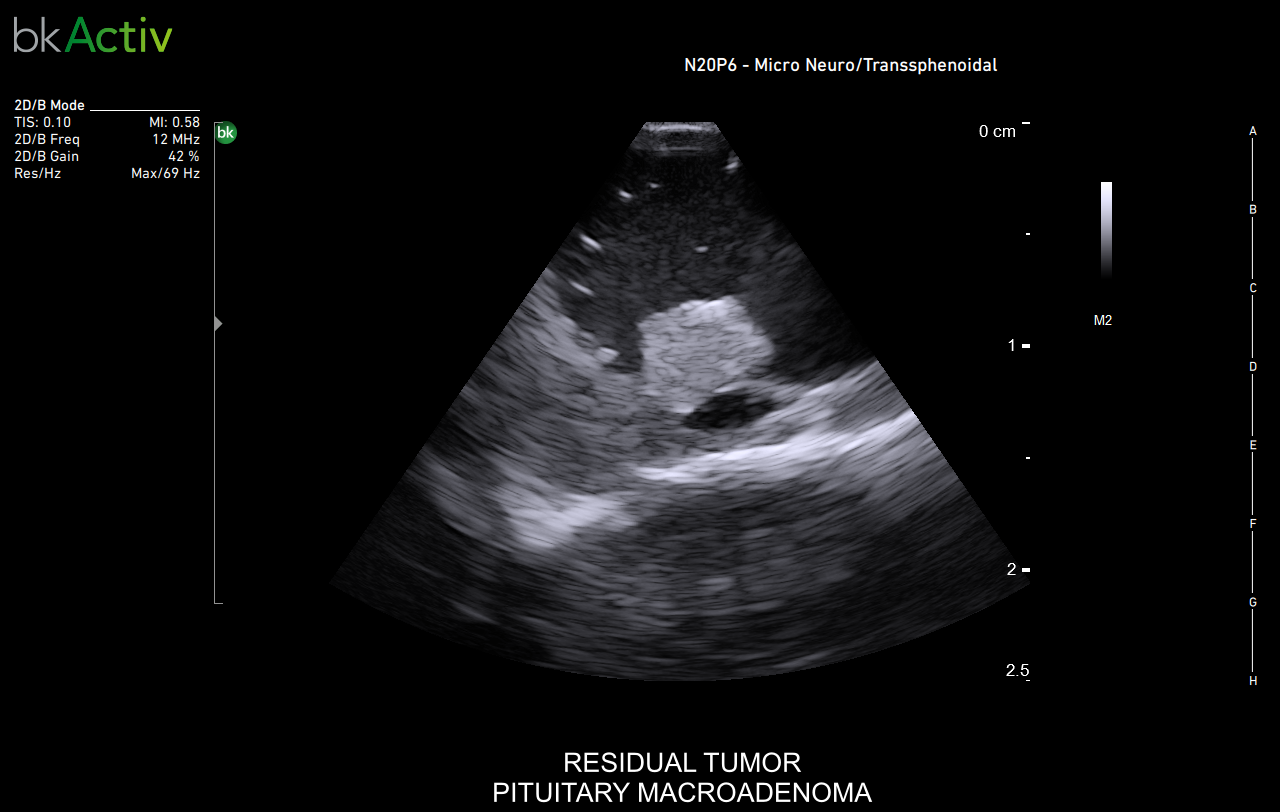

Neurosurgery and Spine

Improved algorithms that automatically allow uniform image resolution, greater details around lesion borders and at larger depths, and enhanced penetration, spatial resolution, and near field image quality.